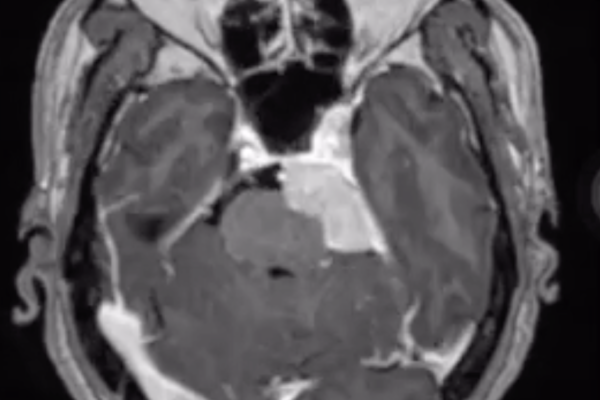

この腫瘍は聴神経から発生する良性の腫瘍(神経鞘腫)で、小脳橋角部という部分に発生するものです。聴神経には聴覚に関係する神経(蝸牛神経)と平衡感覚に関する神経(前庭神経)があり、前庭神経から発生するものが多いとされています。